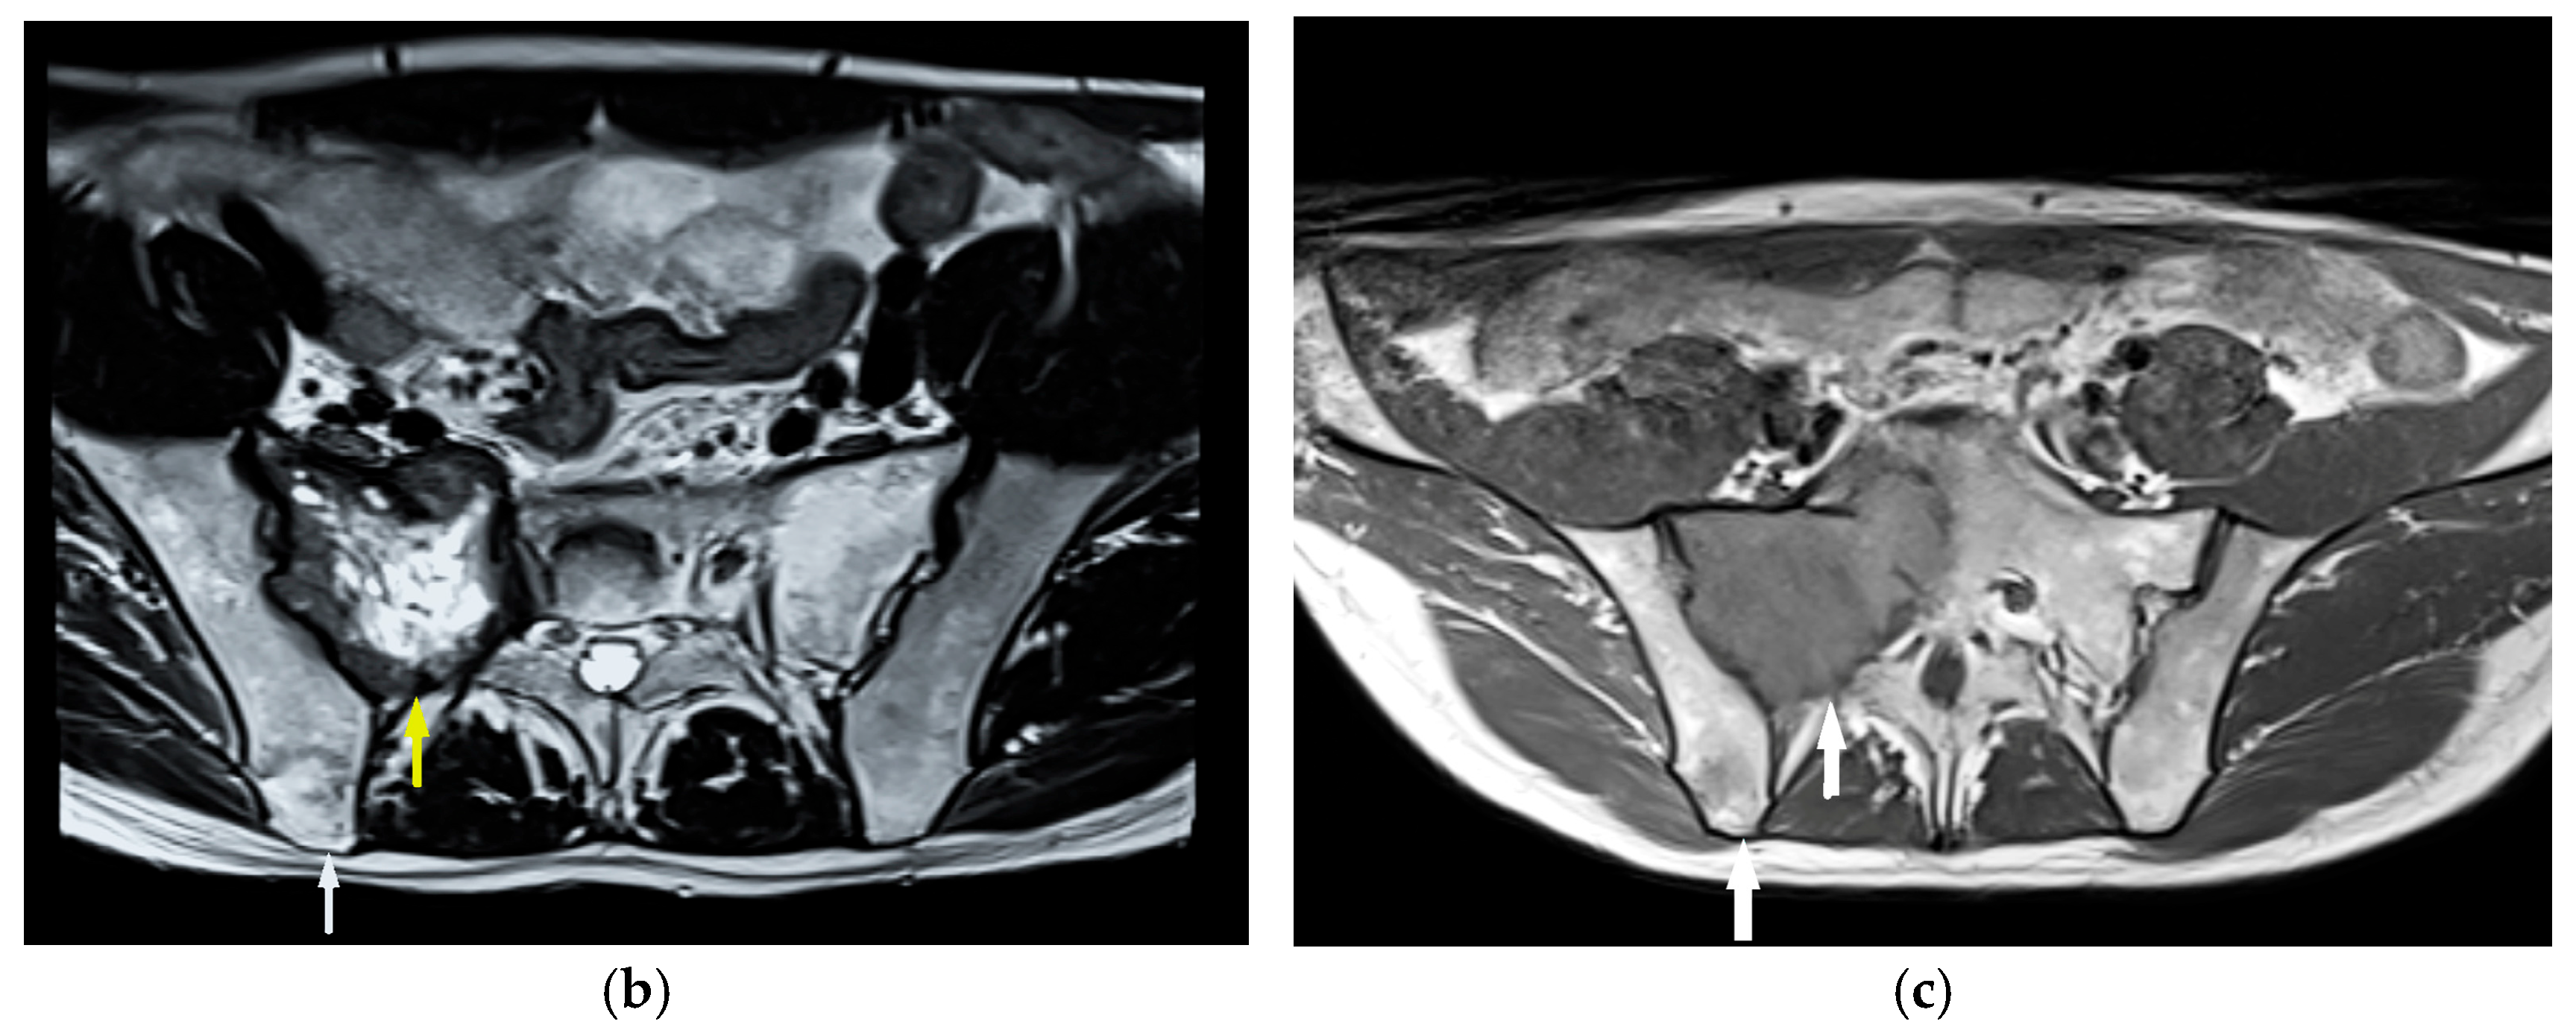

Sabljak, P.; Djuric-Stefanovic, A.; Bubanja, M.; Odalovic, S.; Ivanovic, N.; Mitrovic-Jovanovic, M.; Skrobic, O. High-Risk Esophageal GIST: Imaging and Therapeutic Impact on Atypical Metastatic Lesions. Diagnostics 2025, 15, 1802. https://doi.org/10.3390/diagnostics15141802